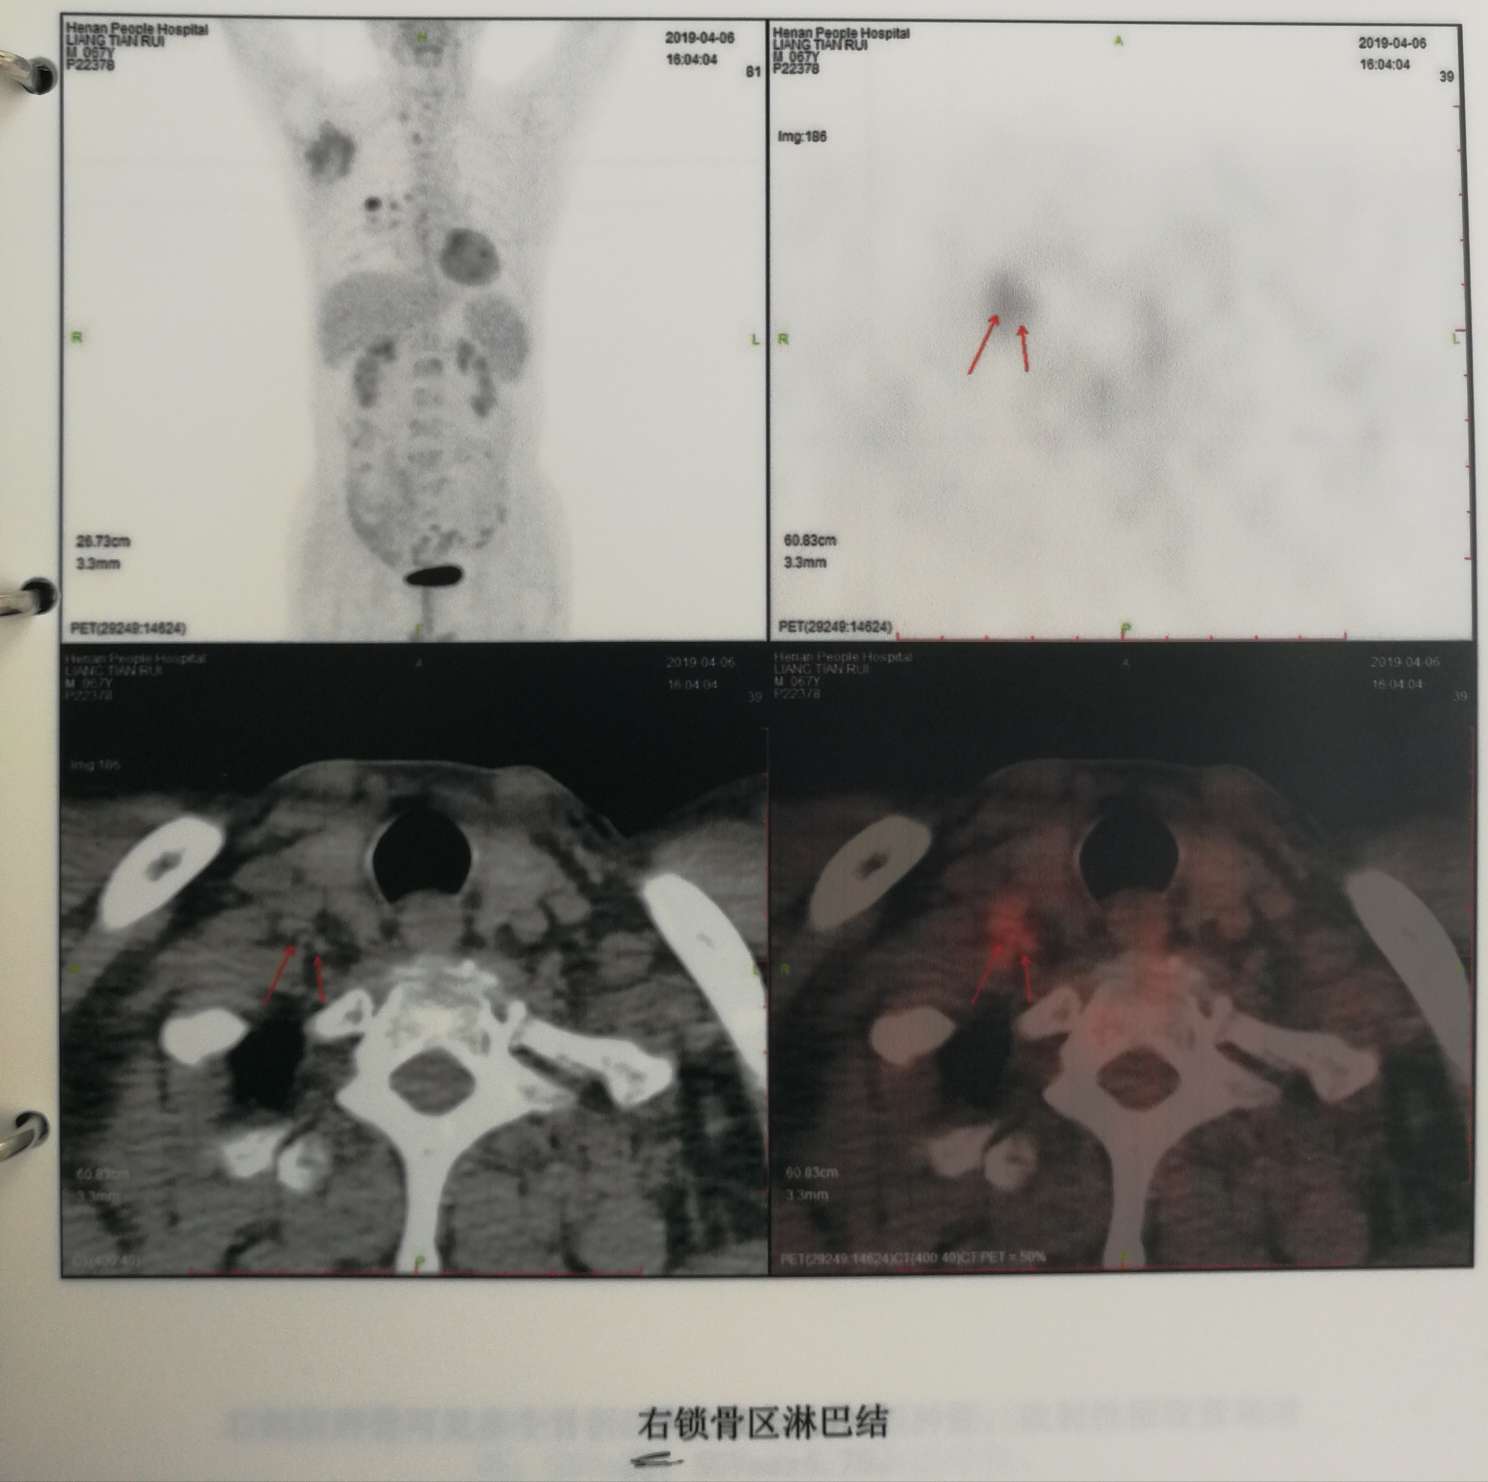

PET-CT显示淋巴结多处转移,诊断为肺腺癌3B期,不能手术。

而后转院到省人民医院,肺部穿刺活检确定为肺腺癌。